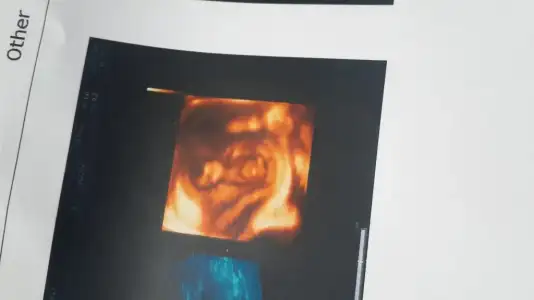

[QUOTymalab, post: 39949718, member: 666650"]Eki Görüntüle 1454685

Benim bebesin cinsiyeti ne olabilir arkadaşlar yorumlayabilir misiniz :) 11 hafta[/QUOTE]

Bana kesin kiz gibi geldi .. benimkine cok benziyo :)))

Benim bebesin cinsiyeti ne olabilir arkadaşlar yorumlayabilir misiniz :) 11 hafta[/QUOTE]

Bana kesin kiz gibi geldi .. benimkine cok benziyo :)))

Kesin kiz diyebilirim :))Eki Görüntüle 1454685

Benim bebesin cinsiyeti ne olabilir arkadaşlar yorumlayabilir misiniz :) 11 hafta

Erkek gibi ...

Net deil ama erken bak bi yukarfaki resimde 11 hafta ama cok netKizlar benm bebisime de yorum yapar misiniz dr ikili taramada solemedi tahminini merak ediyorum :)11+4burda Eki Görüntüle 1454687 Eki Görüntüle 1454687

Ama erkege benziyoKizlar benm bebisime de yorum yapar misiniz dr ikili taramada solemedi tahminini merak ediyorum :)11+4burda Eki Görüntüle 1454687 Eki Görüntüle 1454687